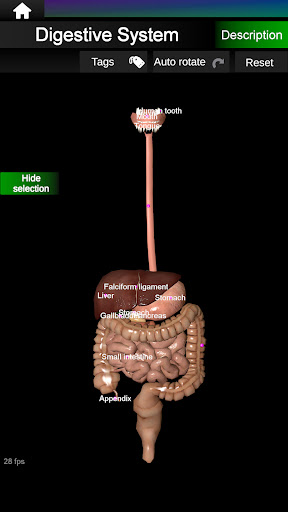

Menampilkan model anatomi 3D dari organ utama tubuh manusia dan penjelasannya masing-masing.

Apa yang ada di aplikasi?

* Sistem pencernaan, termasuk lambung, usus kecil, usus besar, dan animasi sistem ini.

* Mudah diakses dan dinavigasi (zoom, rotasi 3D).

* Sembunyikan atau tampilkan informasi.

* Deskripsi masing-masing organ.